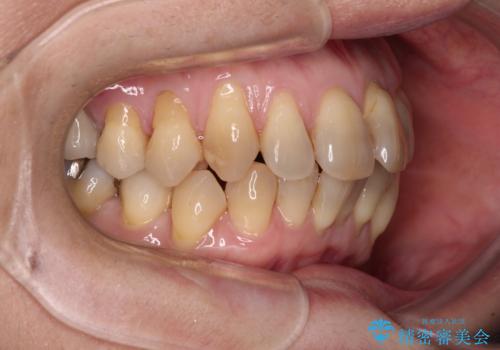

- 上下前歯のデコボコと、奥歯の銀歯を気にして来院された患者様です。

仕事柄あまり目立つ装置は付けることは避けたいとのことで、インビザラインによるマウスピース矯正を行うこととしました。

概ね歯列が整ったところで銀歯の全てをセラミッククラウンなどに置き換え、その後インビザラインを1セット使用して仕上げていくこととしました。